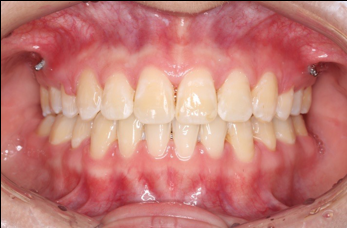

2018.11.14  术后侧面改善明显,露龈笑改善明显,笑弧笑线协调,颏部肌肉紧张度明显改善

2018.11.14  术后磨牙尖牙I类关系,中线齐,覆合,覆盖正常

2019.08.06  术后  10个月复查

宏观评价:面部对称,面下三分一比例协调,上下唇凸度正常,上颌牙列内收转矩控制良好,下颌后缩改善,颏唇沟变得更加柔和,术后达到基本直面型。

迷你观评价:上下牙齿中线与面中线对齐,笑弧协调,微笑时牙龈暴露量正常,微笑时横向正常,左右唇基本对称。

微观评价:牙齿整齐,咬合关系良好,上下前牙转矩及突度控制良好,磨牙关系I类,尖窝咬合关系良好,OB,OJ正常。